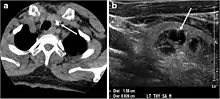

Fig. 16. Midline ectopic thyroid with Hashimoto's thyroiditis in a 49-year-old female patient. a Transverse greyscale ultrasound shows a 1.6 × 0.8 cm solid, well-defined, heterogeneous area (white arrow) in the midline, superior to the thyroid gland. It is iso-echogenic to the thyroid gland with no definite connection to the thyroid gland. b Transverse colour Doppler ultrasound shows significant increase in vascularity. c Axial enhanced neck CT scan at the level of thyroid cartilage demonstrates midline infrahyoid hyperdense soft tissue mass (white arrow) embedded within the strap muscle.[1]